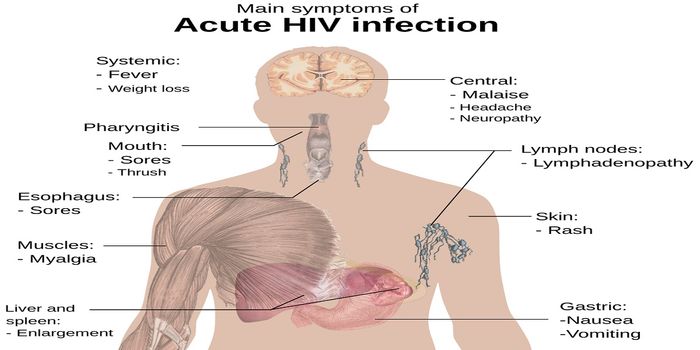

MAY 08, 2019Health & MedicineThe ability to diagnose an acute HIV-1 infection before there are detectable antibodies to HIV 1/2 is critical to making ...